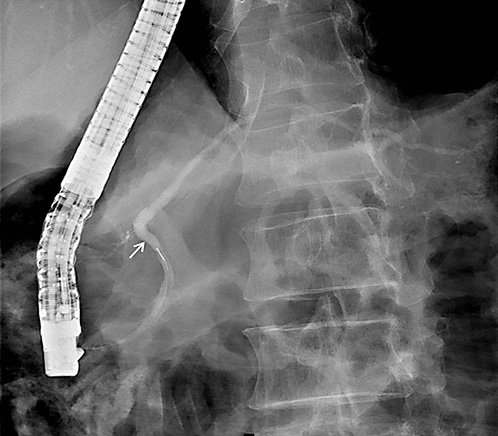

On ERCP, the Wirsungogram identified a point of ductal leak-age in the body of the pancreas, with contrast spreading to the middle of the column (most likely to the pseudocyst lumen) (Fig. 3). Pancreatic sphincterotomy and placement of a double-flanged straight 5-Fr plastic stent with 9 cm (the longest one avail-able in the unit) in the duct of Wirsung, up to the ductal disruption site (Fig. 4), were performed.

Fig. 3 Wirsungogram performed on the first endoscopic retrograde cholangiopancreatography, revealing a ductal leakage in the body of pancreas (white arrow).